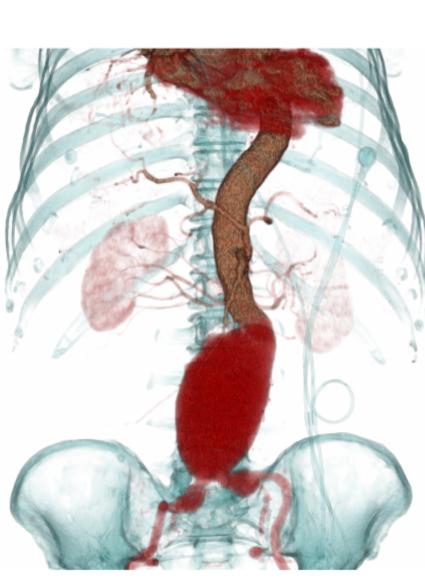

增强后:腹主动脉下段至左右髂总动脉上端明显扩张,最宽处约6.8cm,上下径约为13cm,成瘤样改变,边界清楚,形态规整。

后重建图像就是直观